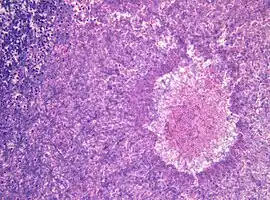

Histopathology of aspergilloma, H&E staining -

Although most fungi—and especially Aspergillus—fail to grow in healthy human tissue, significant growth may occur in people whose adaptive immune system is compromised, such as those with chronic granulomatous disease, who are undergoing chemotherapy, or who have recently undergone a bone marrow transplantation. Within the lungs of such individuals, the fungal hyphae spread out as a spherical growth. With the restoration of normal defense mechanisms, neutrophils and lymphocytes are attracted to the edge of the spherical fungal growth where they lyse, releasing tissue-digesting enzymes as a normal function. A sphere of the infected lung is thus cleaved from the adjacent lung. This sphere flops around in the resulting cavity and is recognized on x-ray as a fungus ball. This process is beneficial as a potentially serious invasive fungal infection is converted into surface colonization. Although the fungus is inactivated in the process, surgeons may choose to operate to reduce the possibility of bleeding. Microscopic examination of surgically removed recently formed fungus balls clearly shows a sphere of dead lung containing fungal hyphae. Microscopic examination of older lesions reveals mummified tissue which may reveal faint residual lung or hyphal structures.[4]